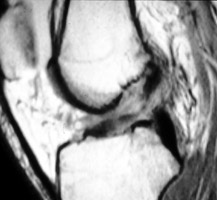

ACL Tear

The anterior cruciate ligament runs obliquely within the lateral aspect of the intercondylar notch, attaching to the inner aspect of the lateral femoral condyle proximally and to the anterior aspect of the intercondylar eminence of the tibia distally. An anterior cruciate ligament-deficient knee allows the tibia to undergo subluxation anteriorly relative to the femur. This is the MR equivalent of the anterior drawer sign.